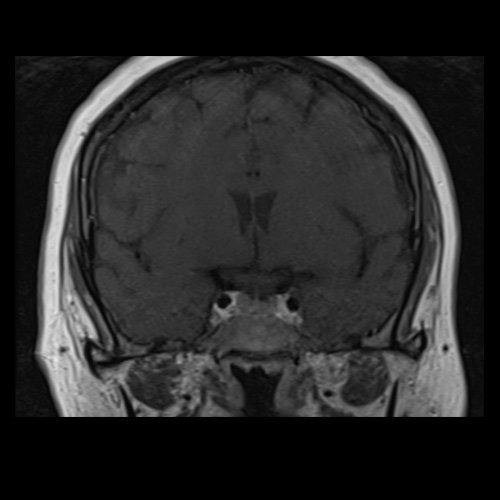

RMN de cráneo con contraste endovenoso (21/02/26) Corte coronal en secuencia T1: sin alteraciones en región selar.

• RMI de cráneo con contraste EV (21/02/26):  Las cavidades ventriculares presentan tamaño y morfología normal. Las estructuras la línea media se hallan en su topografía habitual. A nivel de la fosa posterior el cuarto ventrículo se encuentra en línea media. Bulbo, protuberancia y mesencéfalo sin alteraciones. Relación sustancia gris blanca respetada. No se observan efectos expansivos. El examen de difusión no muestra alteraciones. El efecto FLAIR no muestra alteraciones. La secuencia SWI no muestra alteraciones. No se visualizan alteraciones en proyección, de la región selar, el quiasma óptico y senos cavernosos. No se observan realces patológicos tras la administración de gadolinio.